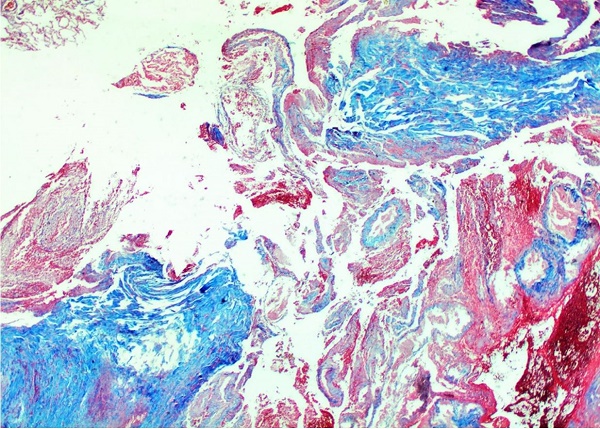

External examination revealed a cachectic corpse with cutaneous and mucosal pallor and thoracotomy in the posterolateral region of the right thorax. Internal examination revealed mucosanguinolent fluid in the trachea and bronchi. The right lung weighed 355 g (reference range = 360-570g1) and contained an abscess in the lower lobe, measuring 12.5 × 8.5 cm. The right lower lobar pulmonary artery also harbored a ruptured aneurysm (Figure 4), which was later confirmed by microscopy with the aid of histochemical staining (Figure 5).

Microscopic examination of the lung revealed extensive liquefactive necrosis, associated with dense purulent inflammation (Figures 66D) and infiltration of filamentous fungi and spores (Figures 77B). Sparse foci of bronchopneumonia were detected on the remaining lung parenchyma. Other organs showed generalized visceral pallor, mild hydrocephalus ex-vacuo, and mild cerebral atrophy, with no additional pathology in the remaining organs. Death was attributed to massive pulmonary hemorrhage due to the rupture of the right lower lobar artery aneurysm, resulting from a chronic lung abscess formed in the right lower lobe.